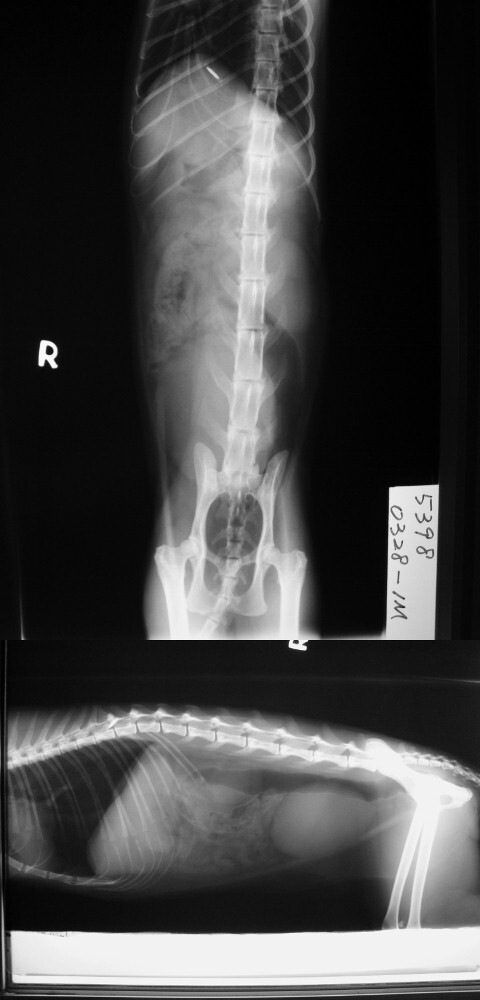

主題: 0327壽山收容所 消瘦及脫水 額頭、前肢有脫毛,皮膚病 申請者姓名: 劉素鳳 花色: 申請日期: 2013-04-25 07:20:03 申請者部落格: 申請者臉書網址: 所在縣市/合作醫院: 高雄市/樂生動物醫院 治療費用: 7300元 需求人數: 8人 已結案 (2013-06-27 14:33:45) 報名人員: grace0314(已付款)、Melody Wu(已付款)、Karen Hsieh(已付款)、Wei-wen Chang(已付款)、Elaine Yang(已付款)、Stacey Ma x2(已付款)、Rosa Lin(已付款)、 候補人員: 動物病情說明: 0328-1M 已結紮,消瘦及脫水

血液生化及電解質 1500

X光片 300*2= 600

住院(3/28~4/6) 300*9= 2700

點滴(3/28~4/1) 300*5=1500